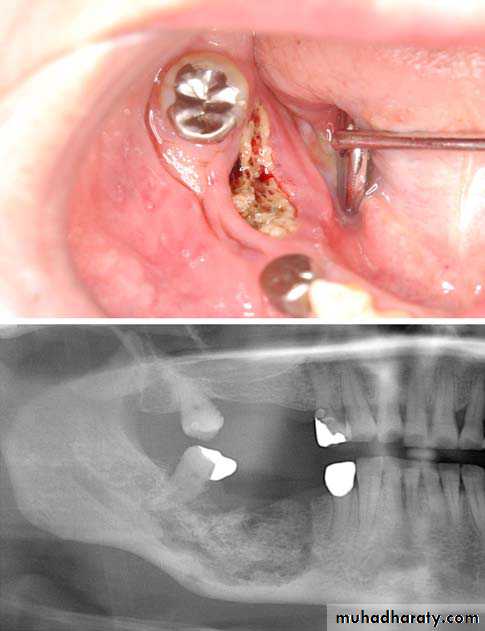

Extraction of /6, showing the typical destructive appearance (solid arrow),

resulting in a pathological fracture (open arrow). Radiotherapy had been given several years previously

(BRONJ). Exposed necrotic bone is seen at the lingual side of the mandibular right second molar. A lesion with osteolysis and osteosclerosis extends from second molar to first premolar region